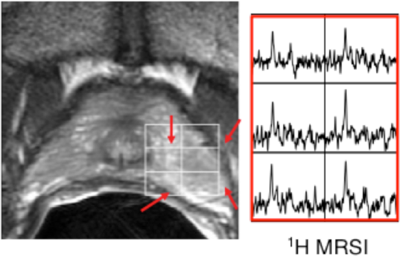

Metabolic Imaging

Metabolic imaging, also called MR spectroscopy imaging or 1H MRSI, measures concentrations of important chemicals (metabolites) within the body. It has been shown to improve the identification and characterization (location, size, and aggressiveness) of prostate cancer in patients.